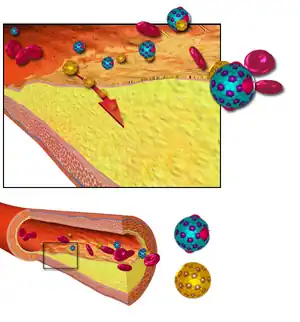

Atherosclerosis is a pattern of the disease arteriosclerosis,[8] characterized by development of abnormalities called lesions in walls of arteries. These lesions may lead to narrowing of the arteries' walls due to buildup of atheromatous plaques.[9][10] At onset there are usually no symptoms, but if they develop, symptoms generally begin around middle age.[1] In severe cases, it can result in coronary artery disease, stroke, peripheral artery disease, or kidney disorders, depending on which body parts(s) the affected arteries are located in the body.[1]

Atherogenesis is the developmental process of atheromatous plaques. It is characterized by a remodeling of arteries leading to subendothelial accumulation of fatty substances called plaques. The buildup of an atheromatous plaque is a slow process, developed over a period of several years through a complex series of cellular events occurring within the arterial wall and in response to a variety of local vascular circulating factors. One recent hypothesis suggests that, for unknown reasons, leukocytes, such as monocytes or basophils, begin to attack the endothelium of the artery lumen in cardiac muscle. The ensuing inflammation leads to the formation of atheromatous plaques in the arterial tunica intima, a region of the vessel wall located between the endothelium and the tunica media. The bulk of these lesions is made of excess fat, collagen, and elastin. At first, as the plaques grow, only wall thickening occurs without any narrowing. Stenosis is a late event, which may never occur and is often the result of repeated plaque rupture and healing responses, not just the atherosclerotic process by itself.[62]